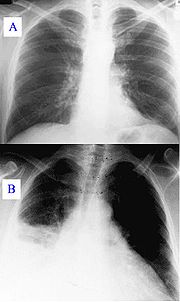

Уже не первый год этот день становится началом старта целого комплекса событий и мероприятий, направленных на то, чтобы каждый житель города смог получить больше знаний по профилактике туберкулеза, напомнить тюменцам о необходимости ежегодного прохождения флюорографических осмотров. С 24 марта по 23 апреля, все желающие, независимо от места проживания смогут бесплатно пройти флюорографическое обследование органов грудной клетки. Для этого с понедельника по  пятницу с 8-00 до 17-00 ча...